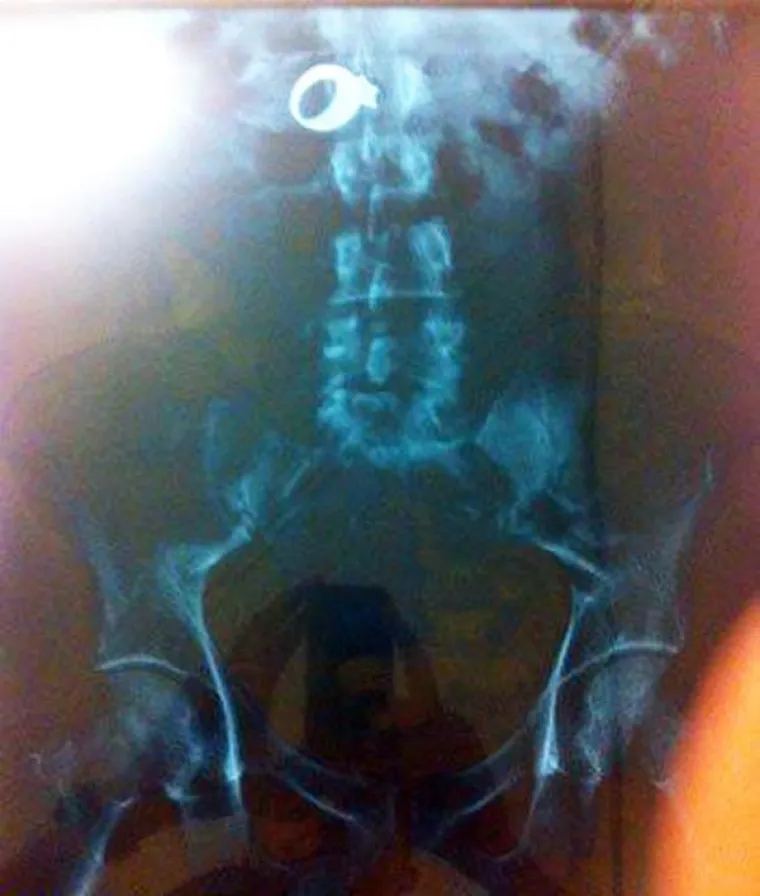

Vjenčani prsten.